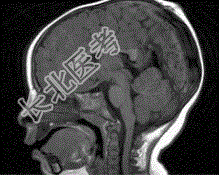

- 单项选择题男孩,1岁。有头皮损伤史, CT检查,最可能的诊断是

A、脑膨出

B、胼胝体发育不全

C、Dandy-Walker综合征

D、狭颅症

E、脑积水